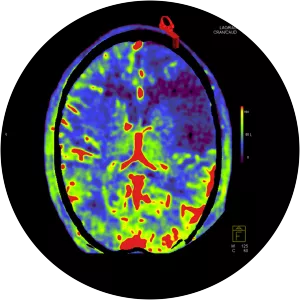

Neuroradiology is a subspecialty of radiology focusing on the diagnosis and characterization of abnormalities of the central and peripheral nervous system, spine, and head and neck using neuroimaging techniques.